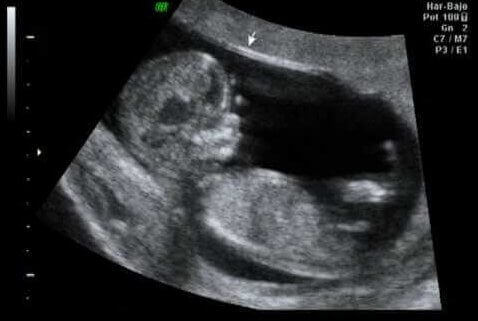

Échographie à la douzième semaine de la grossesse

Point culminant du premier trimestre, la douzième semaine est généralement le point idéal pour effectuer un contrôle sur ce tiers de la grossesse : la première échographie. Il est ainsi vérifié que les organes se développent correctement.

On vérifie également la taille et le poids du bébé, ainsi que la présence de la translucidité nucale, le liquide que tous les fœtus ont dans le cou.

Il s’agit d’un moment très important, car les spécialistes affirment qu’entre 60% et 70% des problèmes de malformation que le fœtus peut présenter peuvent être détectés à ce stade.

D’autre part, l’épaisseur de la nuque du fœtus se mesure et sa valeur fait partie du dépistage du premier trimestre. En effet cela permet de détecter le risque d’anomalie dans le nombre de chromosomes (connu sous le nom d’aneuploïdies), notamment la trisomie 21 ou le syndrome de Down.

La première échographie permet de détecter entre 60% et 70% des problèmes de malformation du fœtus.

La partie excitante de l’échographie, en plus de percevoir la première activité du fœtus, est l’estimation de la date prévue pour l’accouchement. Quoi qu’il en soit, et sans aucune intention de vous décevoir, cela n’est vrai que 5% du temps.